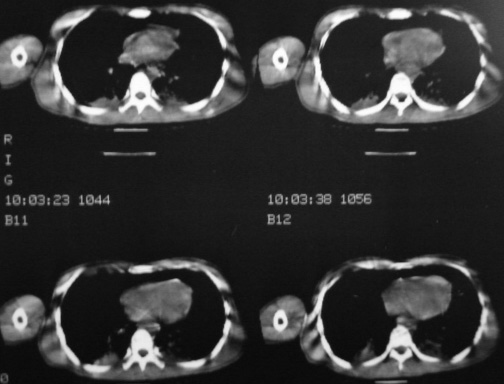

男,18岁,车祸20小时后胸ct.血氧饱和度80,呼吸45次/分.

1:双肺挫裂伤,以双下肺明显。

2:纵隔气肿。

1:两侧创伤性湿肺(撕裂伤)。

2:纵隔气肿.